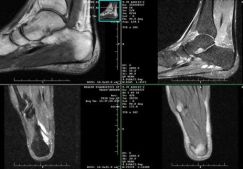

МРТ — современный и наиболее информативный диагностический метод. Он позволяет визуализировать повреждения костей и связочно-сухожильного аппарата. На полученных снимках МРТ коленного сустава хорошо видны все нарушения целостности составляющих его элементов.

Здоровые ткани выглядят на полученных изображениях в виде слабоокрашенных участков. Они четко дифференцированы в зависимости от своей плотности. Врач-диагност без затруднений выделяет нервное или мышечное волокно, соединительные структуры коленного сустава. Поврежденные элементы определяет по их окрашиванию, хорошо заметному на фоне здоровых тканей. Что показывает МРТ коленного сустава:

- сухожилие просматривается на изображениях значительно лучше мениска. Хорошо заметны воспалительные утолщения, обозначаемые в медицинской практике термином «колено бегуна». Под воздействием магнитного поля они становятся источником отраженного аномального интенсивного сигнала.